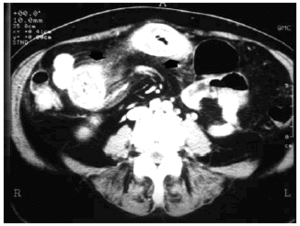

Paciente de 72 años, con antecedentes de hipertensión arterial y fibrilación auricular crónica, hipocoagulada con acenocumarol. Consulta por dolor abdominal cólico en mesogastrio, náuseas y vómitos, presentando en la exploración discreta distensión abdominal y extensa equimosis en la pierna derecha como únicos hallazgos relevantes. El INR inicial fue de 11; tras administrar plasma y vitamina K parenteral el INR se redujo a 1,8. La hemoglobina inicial fue de 11,5 g/dl, con valor valle de 8,2 g/dl a las 24 h. En la tomografía axial computarizada abdominal (figs. 1 y 2) se observó líquido libre perihepático y en pelvis, así como un largo trayecto de asa de intestino delgado con paredes engrosadas (flechas), compatible con hemorragia intestinal intramural. La paciente evolucionó de forma satisfactoria con tratamiento conservador, incluyendo fluidoterapia, analgésicos y aspiración nasogástrica, sin incidencias posteriores. El diagnóstico fue de hemorragia intramural intestinal, sobredosificación por acenocumarol.

Figura 1